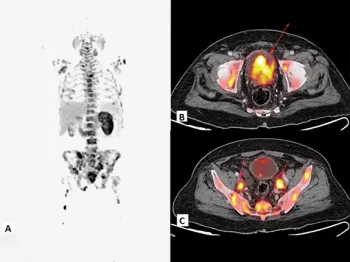

In 2020, the FDA approved the first PSMA-targeted PET imaging treatment for men with prostate cancer. PSMA (prostate-specific membrane antigen) is a protein found mainly on prostate cancer cells, and targeting PSMA may make it easier to find prostate cancer during a PET scan. Doctor Giuseppe Esposito of Medstar Georgetown University Hospital shares great insight into PSMA PET Imaging and prostate cancer.This session was part of our VIRTUAL ZERO Prostate Cancer Summit, a free online event that took place from February 28 to March 4, 2021.Watch